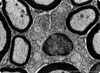

What is this?

Transmission electron microscopy image